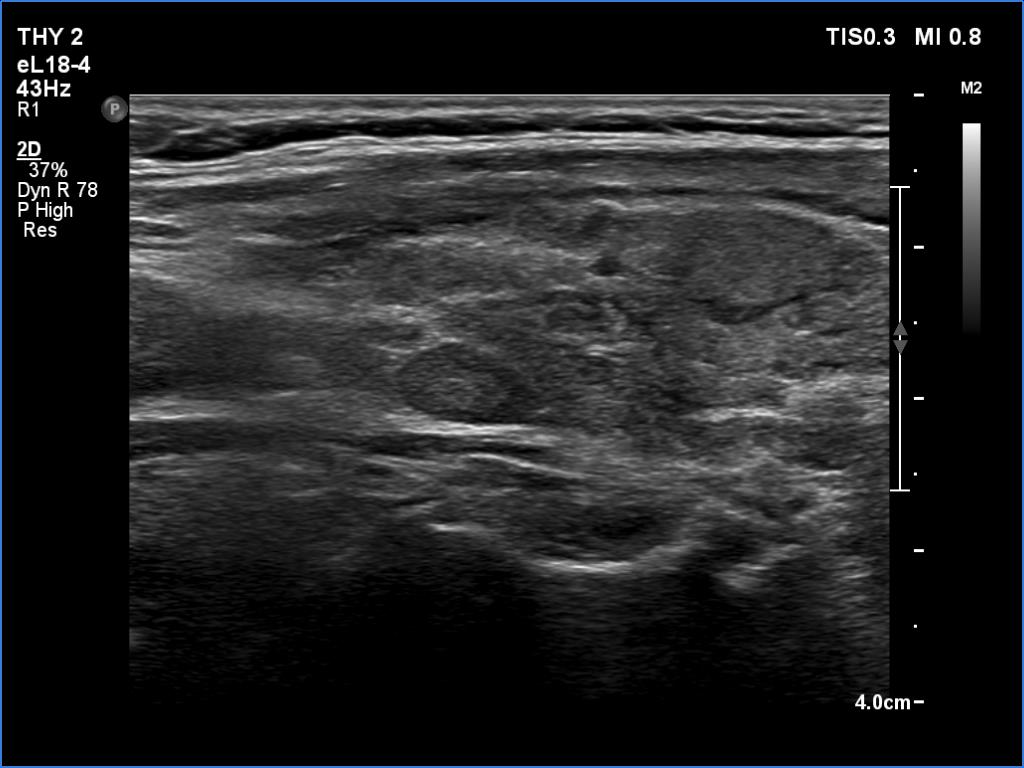

Ultrasonography. The thyroid was minimally hypoechoic and had several discrete areas of various echogenicities. None of these lesions corresponded to true nodule.